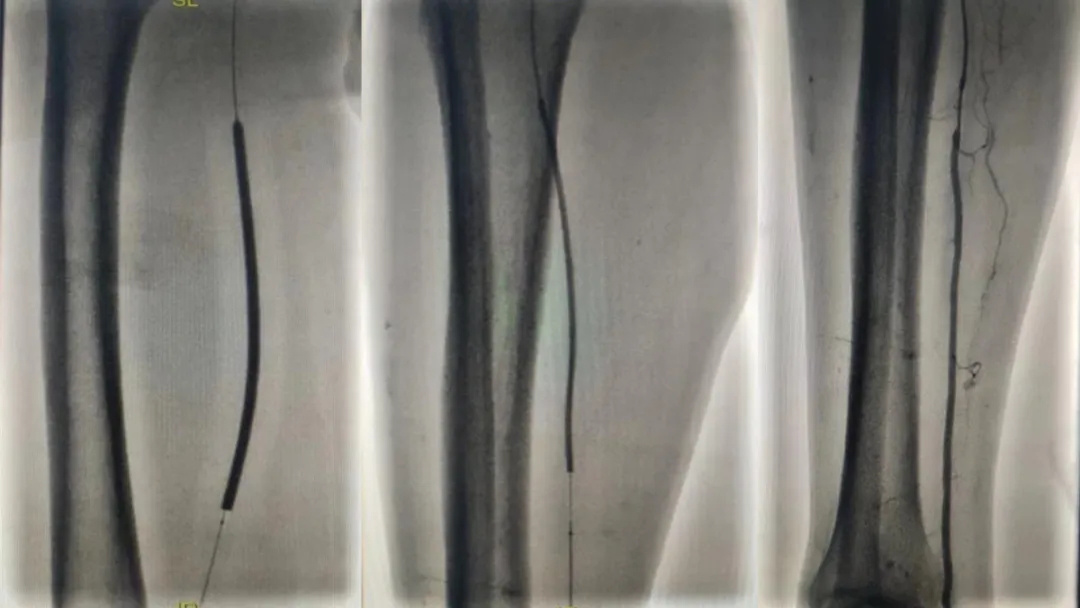

然后

他們巧妙運(yùn)用

先進(jìn)的機(jī)械導(dǎo)管和球囊

如精巧的工匠般

小心翼翼地

疏通著“生命之路”